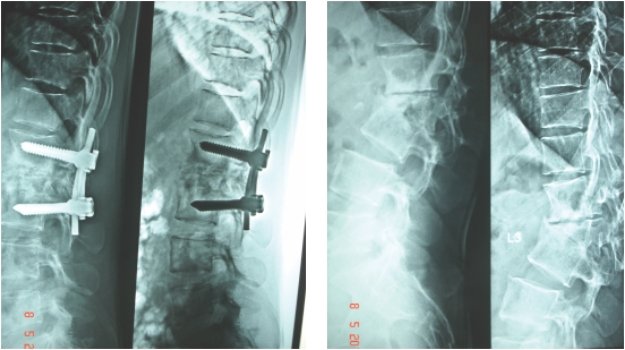

he was operated from front of the neck, a new vertebra(tricortical bone graft) was

put and fixed with plate

Paeditric Koch’s - Spine